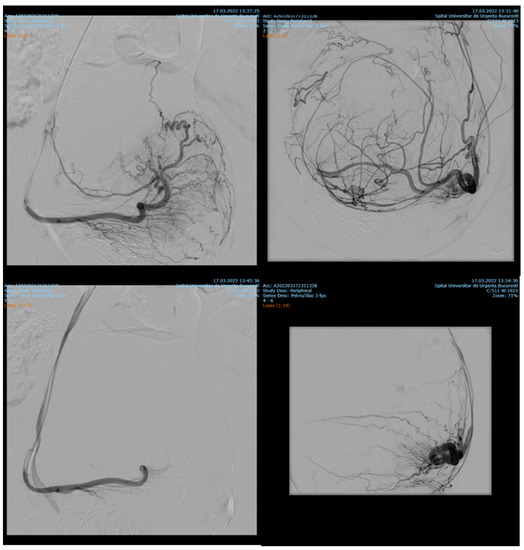

Endovascular procedures were used in 2.29% of cases with ectopic pregnancy (n = 26) (see Figure 4 and Figure 5), 1.23% of patients with arteriovenous malformation (n = 14) (see Figure 6), and 0.52% of patients with major hemorrhage of obstetrical causes (n = 6).

Figure 4. Pelvic artery embolization for cervical ectopic pregnancy.

Figure 5. Pelvic artery embolization for C-scar ectopic pregnancy.